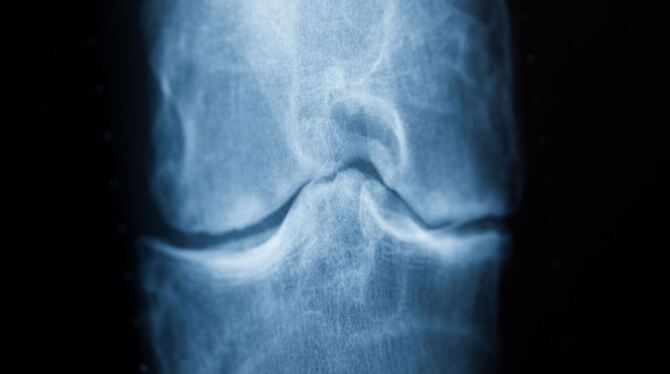

In Deutschland haben laut Deutscher Arthrose-Hilfe etwa fünf Millionen Menschen Beschwerden durch Arthrose. Bei dieser Erkrankung baut sich das Knorpelgewebe im Gelenk ab. Ist der schützende Knorpel zerstört, führt das zu starken Schmerzen. Betroffene können das Knie nicht mehr richtig belasten, treiben oft weniger Sport und sind im Alltag eingeschränkt.

Arthrose tritt meist mit zunehmendem Alter auf und lässt sich nicht heilen. Behandelt wird mit Physiotherapie, Schmerzmitteln und in den schwersten Fällen mit einer Kniegelenkersatz-OP. Hilfreich ist laut der Arthrose-Hilfe Bewegung ohne Belastung, »da dadurch der Gelenkknorpel besser ernährt wird, und das Fortschreiten der Arthrose sich verlangsamt«.